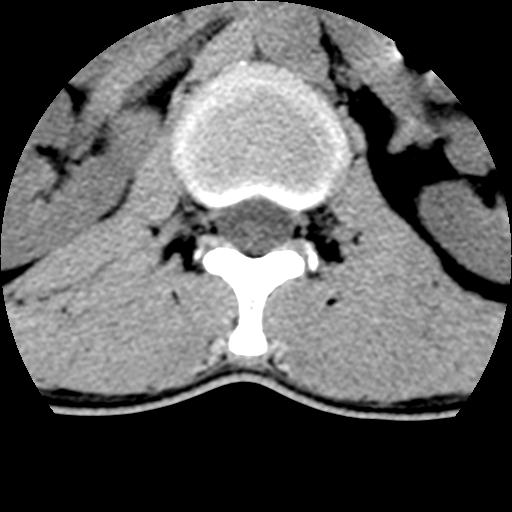

标题: CT10387:男,31岁,胸腰段CT [打印本页]

标题: CT10387:男,31岁,胸腰段CT

男,31岁,从6米高处坠落伤两天,腰背部疼痛,临床要求ct扫描胸10-腰1。请大家帮忙看看骨质有问题吗?

t12、l1锥体前缘轻度楔形变,平扫示椎体前缘骨小梁欠规整,第9幅图示椎体前缘骨质不连续,结合外伤史考虑椎体轻度压缩骨折。

楼主扫描层厚可能较大,每个椎体只有三个层面.

从所示层面分析,无明确骨折征象,象类似病人我个人会建议mri除外骨挫伤.

从上查骨窗第九片椎体前缘皮质显示断裂.压缩骨折?